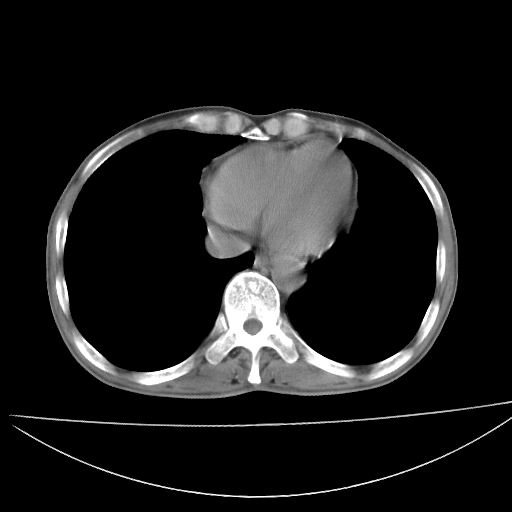

以下是引用杀毒软件在2009-4-28 17:58:00的发言:[br]考虑----左肺慢性肺脓肿形成继发上叶含气不良---抗炎后复查---待排肿瘤所致[br][br][本贴已被 杀毒软件 于 2009-4-28 18:01:26 修改过]